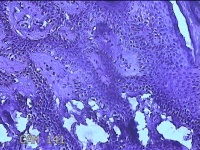

左侧臀部结节

性别

女

年龄

24岁

临床诊断

皮下结节

一般病史

发现左侧臀部结节1年余。

标本名称

大体所见

灰白暗红色带皮肤样结节0.7x0.3x0.2cm一个,表面糜烂,切开结节呈实性,切面灰白暗红色,质软。

图2